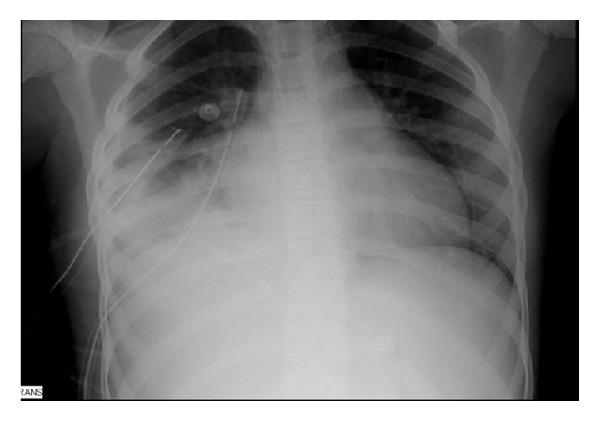

Community-associated methicillin-resistant Staphylococcus aureus (CA-MRSA) is an emerging public health problem worldwide. Severe invasive infections have been described, mostly associated with the presence of Panton-Valentine leukocidin (PVL). In Portugal limited information exists regarding CA-MRSA infections. In this study we describe the case of a previously healthy 12-year-old female, sport athlete, who presented to the hospital with acetabulofemoral septic arthritis, myositis, fasciitis, acetabulum osteomyelitis, and pneumonia. The MRSA isolated from blood and synovial fluid was PVL negative and staphylococcal enterotoxin type P (SEP) and type L (SEL) positive, with a vancomycin MIC of 1.0 mg/L and resistant to clindamycin and ciprofloxacin. The patient was submitted to multiple surgical drainages and started on vancomycin, rifampicin, and gentamycin. Due to persistence of fever and no microbiological clearance, linezolid was started with improvement. This is one of the few reported cases of severe invasive infection caused by CA-MRSA in Portugal, which was successfully treated with linezolid. In spite of the severity of infection, the MRSA isolate did not produce PVL.